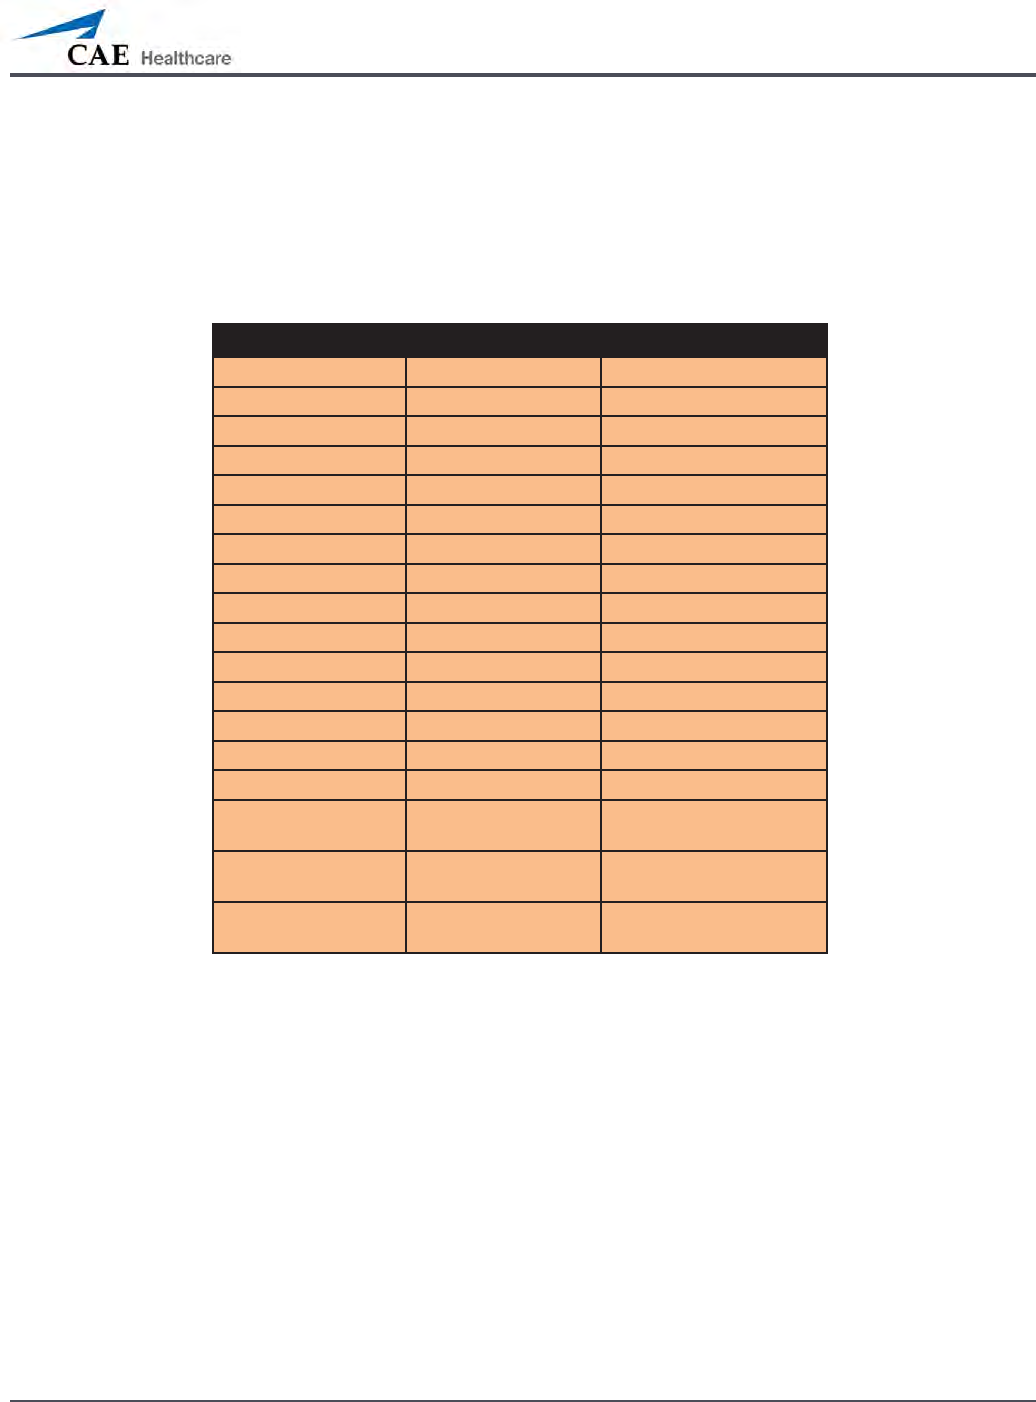

Airway Features

Anatomy, Physiology

and Clinical Signs Clinical Interventions, Patient

Monitoring and Scenarios. Software Control Manual

Control

Realistic Upper

Airway (Oropharynx,

Nasopharynx and Larynx)

(Prehospital only)

Allows direct laryngoscopy, oral and

nasal intubation and use of specialty

airway devices. Simulator detects

and responds appropriately to right

mainstem intubation. Endobronchial

intubation results in unilateral chest

excursion and breath sounds.

None required. None required.

Trachea, Left and Right

Mainstem Bronchi

(Prehospital only)

Tracheal intubation results in bilateral

chest excursion and breath sounds. None required. None required.

Airway Management and

Ventilation

Alveolar and arterial gas concentrations

appropriately reect the ecacy of

ventilation and oxygen administration.

Oxygen

administration input

by the instructor.

VIEW: Respiratory

None required.

Gastric Distention

(Prehospital only)

Esophageal intubation results in gastric

distension and the absence of breath

sounds, chest excursion and CO2 output.

None required. None required.

Breakaway Teeth

(Prehospital only)

Upper front teeth can be dislodged if

laryngoscopy is performed incorrectly. None required. See Breakaway

Teeth

Tongue Edema

(On/O)

Hinders, but does not prevent,

intubation. VIEW: Respiratory None required.

Posterior Pharynx

Swelling

(Prehospital only)

Obstructs view of larynx to prevent

intubation, but allows mask ventilation

“can’t intubate, can ventilate” scenario.

VIEW: Respiratory None required.

Laryngospasm

(Prehospital only)

Closes vocal cords and prevents

intubation and ventilation. When used

with posterior pharynx swelling, creates

a “can’t intubate, can’t ventilate” scenario.

VIEW: Respiratory None required.

Cricothyroid Membrane Allows needle cricothyrotomy,

transtracheal jet ventilation, retrograde

wire techniques and cricothyrotomy.

None required. See

Cricothyrotomy,

132